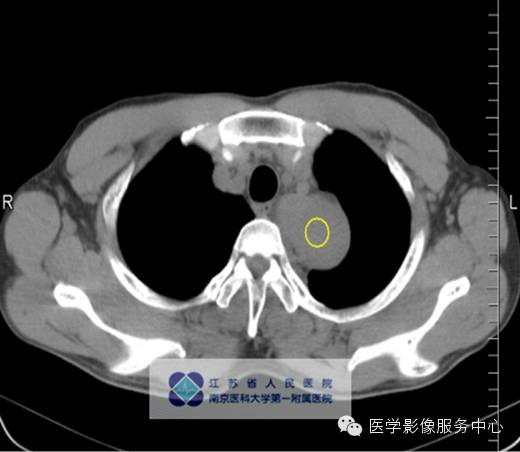

男,27岁,因“查体发现纵隔占位三月余”入院。

影像分析:左上、后纵隔内见类圆形软组织密度增高影,密度尚均匀,边缘清晰,增强扫描均匀强化。

单中心型:大部分为透明血管型,表现为纵隔及肺门圆形或卵圆形较大软组织肿块,边缘光滑锐利可有分叶,多数密度均匀可伴斑点状、树枝状等不同表现钙化。Meador等报道病变强化与病灶大小有关,小于5cm多为均匀强化,大于5cm的多不均匀强化,另外,还与病变的组织学特点如变性、坏死、纤维化的程度有关。

动脉期病灶明显强化,均匀或不均匀,其强化程度可与邻近动脉相仿;

门脉期病灶均匀强化,但增强值小于动脉期,仍高于周边软组织密度;

平衡期病灶持续强化,呈略高或高密度。外周有点状异常增强的小血管,可能滤泡间大量毛细血管增生,周围有滋养血管所致。